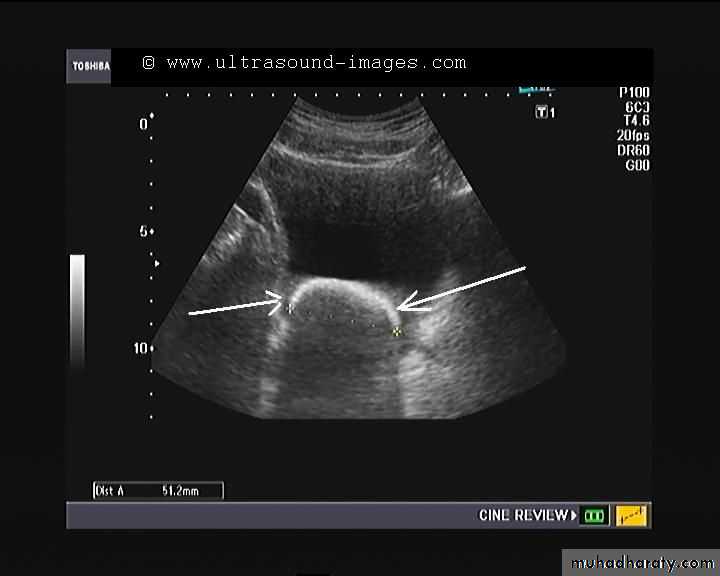

hydronephrosis